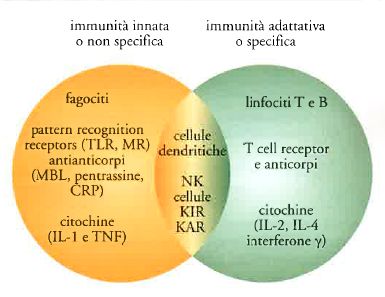

Nlrp12 appartiene alla famiglia di proteine note per lavorare nel sistema immunitario innato che è la prima linea di difesa dell’organismo. La proteina funziona con le cellule T ed altri componenti del sistema immunitario adattivo, per salvaguardare la salute.

Qust’ultimo studio ha dimostrato che nelle celluleT, la proteina Nlrpo12 svolge la stessa funzione antinfiammatoria regolando la produzione di interlichina 4 (IL-4) e altre citochine.